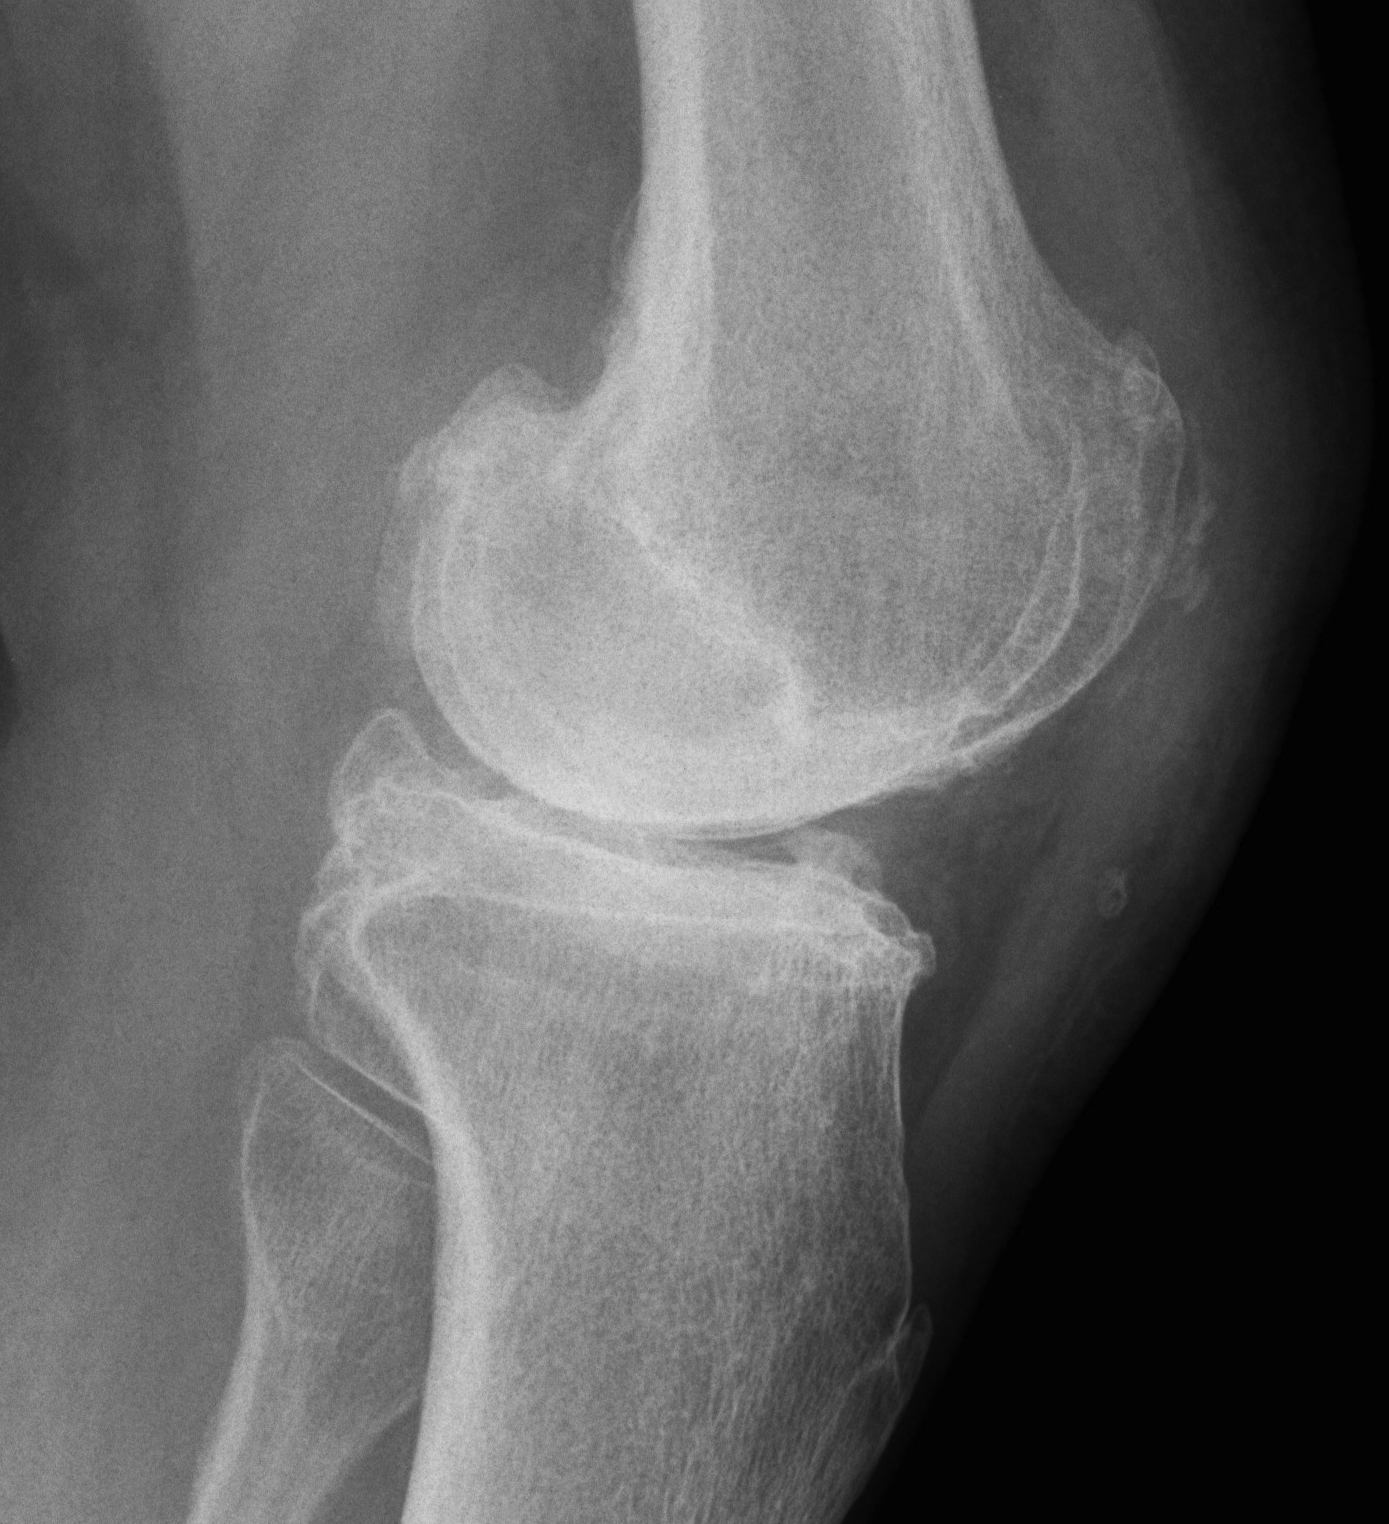

CR / PCL retaining

Known Advantages

1. PCL acts as knee stabiliser

- prevents anterior dislocation of femur on tibia

- provided is correctly balanced

Disadvantages

1. More difficult to balance

- PCL often scarred

- tight in flexion / limited flexion / anterior lift off

- can downsize femoral component, increase posterior slope, recess PCL

2. Increased wear in early designs

- without ACL, rollback is a combination of roll and slide

- for rollback to occur the tibial PE must be relatively flat

- this created high contact stresses and rapid poly wear and failure